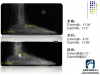

邵某,患者,男性,12岁 , 双足内侧疼痛

距下关节稳定术